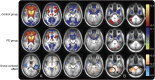

Methods: PD participants without dementia (n = 43) and age-matched controls (n = 22) had lumbar punctures to measure CSF protein levels, Pittsburgh compound B (PiB)-PET imaging, and rs-fcMRI while off medication. Imaging analyses focused on 5 major resting-state networks as well as the striatum.

Results: Participants with PD had significantly reduced sensorimotor functional connectivity, which correlated with reduced CSF levels of α-synuclein. The PD group also had significantly stronger default mode network functional connectivity that did not correlate with CSF β-amyloid (Aβ)42 or PiB uptake. In contrast, default mode network functional connectivity in the control group did correlate with CSF Aβ42 levels. Functional connectivity was similar between groups in the dorsal attention, control, and salience networks.

Conclusion: These results suggest that abnormal α-synuclein accumulation, but not Aβ, contributes to the disruption of motor-related functional connectivity in PD. Furthermore, correlating CSF protein measures with the strength of resting-state networks provides a direct link between abnormal α-synuclein metabolism and disrupted brain function in PD.